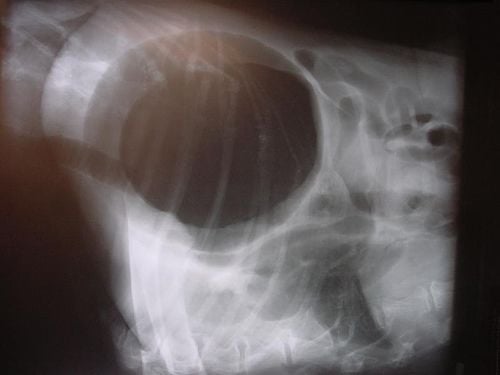

A gyomorcsavarodás különösen nagy testű kutyák életveszélyes betegsége. A gyomor – akár 360 fokos – csavarodása következtében a gyomorszáj és a nyelőcső teljesen elzáródik. A has elülső része nagyon gyorsan, jelentős mértékben kitágul, a kutya öklendezik, hányni azonban nem tud. A gyorsan kialakuló vérkeringési elégtelenség és sokk következtében nagyon gyorsan romlik a beteg állapota, a halál rövid időn belül bekövetkezik. A gyomorcsavarodás tünetei általában annyira jellegzetesek, hogy a diagnózis felállításához nincs is szükség kiegészítő, nyelőcsőszondás röntgenvizsgálatokra. Ezekre amúgy sincs sok idő, mert a vérkeringés összeomlása és a gyomor falának elhalása miatt a halál nagyon gyorsan bekövetkezik. Csakis azonnali műtét és sokkelhárító terápia segíthet. Ez utóbbi az erek feltöltését, és a szívműködés sztrofantinnal történő támogatását jelenti. A hasüreg megnyitását és a felhalmozódott gázok szondán át történő lebocsátását követően, a gyomrot eredeti helyzetébe csavarják vissza. A csavarodás következtében lefűződött lépet, ha nagymértékben károsodott, el kell távolítani. Az újabb csavarodást megelőzendő, a gyomrot – eredeti helyzetében – az oldalsó hasfalhoz rögzítik. A megelőzés érdekében mindig csak kisebb mennyiségeket etessünk, és evést követően ne mozgassuk az állatot. A gyomorvég (pylorus) szűkületét görcsoldó szerekkel kezelhetjük, és naponta többször kisebb mennyiségeket etetünk. Ha ez nem hoz javulást, műtéti úton, két-három metszéssel kell kitágítani a gyomorvég beszűkült részét. Ennek hatására csökken a gyomor kijáratának feszülése és a pépes gyomortartalom akadály nélkül folyhat át a vékonybélbe.